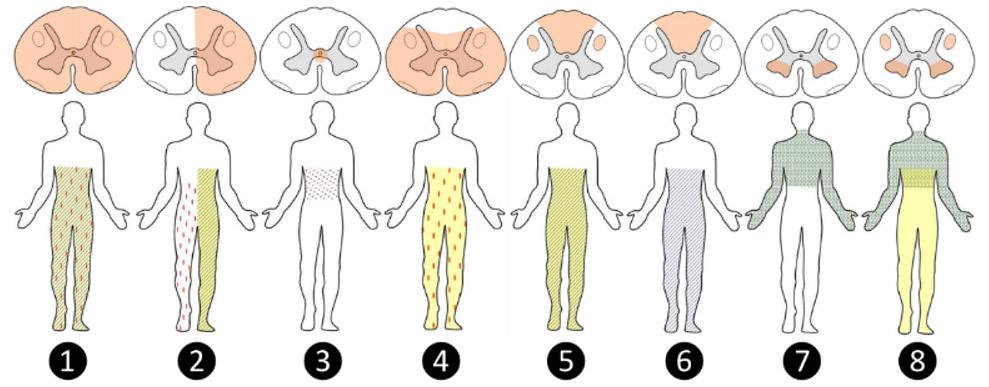

La clínica debido a la lesión de médula espinal dependerá de la región lesionada. Es así que en el siguiente esquema podemos ilustrar las diferentes lesiones.

Esquema de lesiones de médula espinal. Rosado (lesión medular), amarillo (déficit motor piramidal), líneas ondeadas (déficit motor de segunda motoneurona), puntos rosados (alteración se la sensibilidad termoalgésica), líneas oblicuas (alteración de la sensibilidad vibratoria y posicional).

1. Síndrome de sección medular completa

2. Síndrome de hemisección medular (de Brown-Sequard)

3. Síndrome medular central (de Schneider)

4. Síndrome de la arteria espinal anterior

5. Lesión combinada de cordones posteriores y laterales

6. Síndrome de cordones posteriores

7. Síndrome de astas anteriores

8. Lesión combinada de cordones laterales y astas anteriores